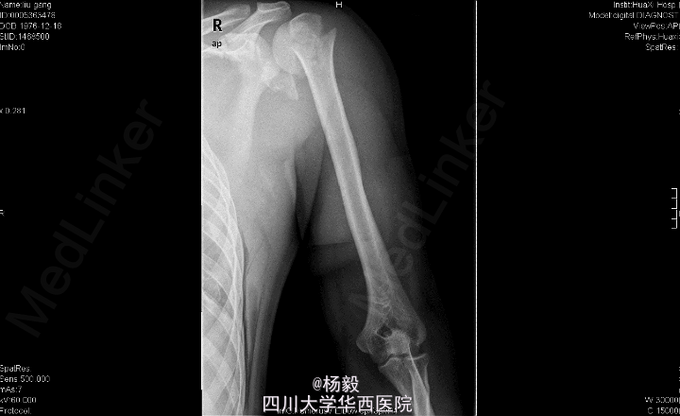

男,33岁11月,因“车祸伤后全身多处疼痛、左上肢活动障碍9小时”入院。 患者自述入院前9小时,被货车撞伤,具体受伤姿势及着力方式不清,患者原发昏迷约5分钟,醒后能回忆受伤情况,患者述胸部及左肩部疼痛,呼吸困难,气促,左上肢感觉麻木,左手伸屈活动受限,患者无恶心呕吐,无咯血,感腹部稍微疼痛,无大小便失禁,其余四肢无活动障碍,曾经当地医院诊治,具体诊断不详,行对症治疗后,患者感呼吸困难加重,为进一步治疗,患者转我院,门诊请胸科会诊后行左侧胸腔闭式引流术,请普外科会诊后,认为腹部无明显指征,暂观察,急诊以“左肩胛骨骨折,左肱骨外科颈骨折,胸腔积液'收住我科。

胸廓左侧胸廓呼吸动度减弱,左胸部腋中线处见一闭式引流管接水封瓶。,双肺叩诊呈清音,双肺呼吸音清,未闻及干湿啰音及胸膜摩擦音。腹部外形正常,全腹柔软,上腹压痛,无反跳痛,腹部未触及包块,肝脏肋下未触及,脾脏肋下未触及,双肾未触及。双下肢无水肿。专科检查:视:左上臂夹板外固定,解开夹板后见左肩部及左上臂肿胀,左上臂下段外侧见约5cm*8cm皮肤擦伤。触:左肩胛部及左肩部压痛,左前臂下段 以远痛温触觉较对侧减退,左桡动脉能扪及,左手甲床微循环正常。动量:左肩关节、左肘关节、左腕关节及左手指各关节伸屈活动受限。 辅助检查:X片检查示:左肩胛骨及左肱骨上段骨折,左侧多发肋骨骨折,左肺挫伤,左胸腔积液,脾区高密度影。

初步诊断:1、左肩胛骨粉碎性骨折。2、左肱骨外科颈骨折伴神经损伤。3、左侧胸腔积液闭式引流术后。4、左侧多发肋骨骨折。5、左肺挫伤。6、脾脾脏损伤? 全麻下行左肱骨外科颈骨折切开复位内固定术。